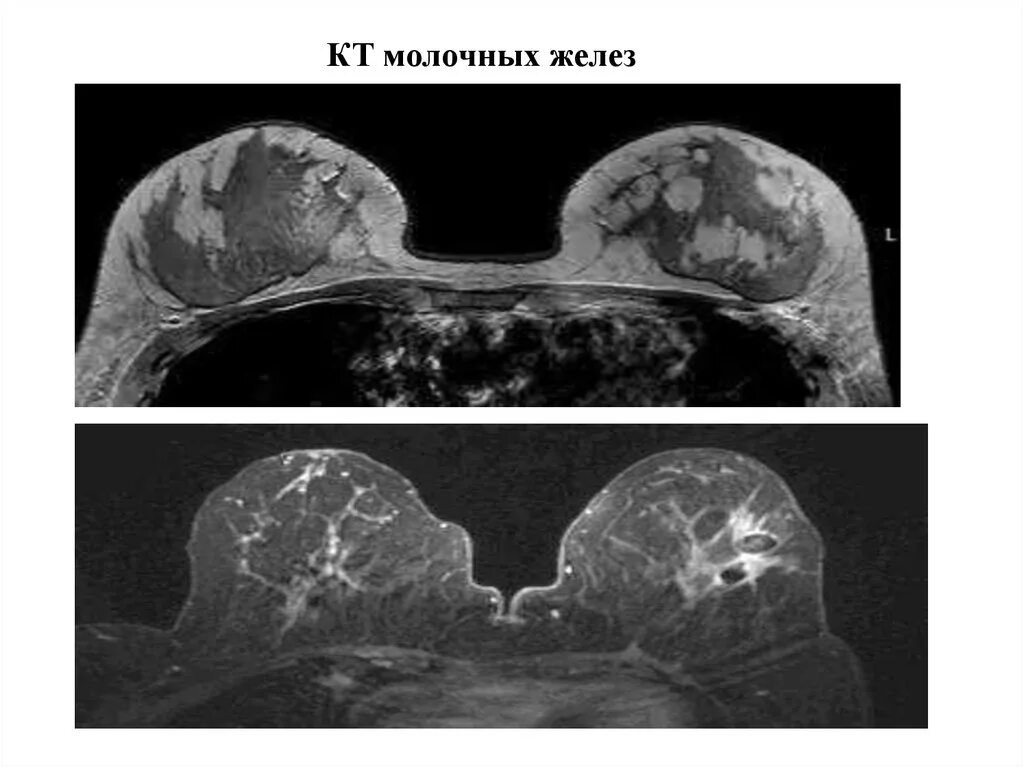

Мрт молочных желез